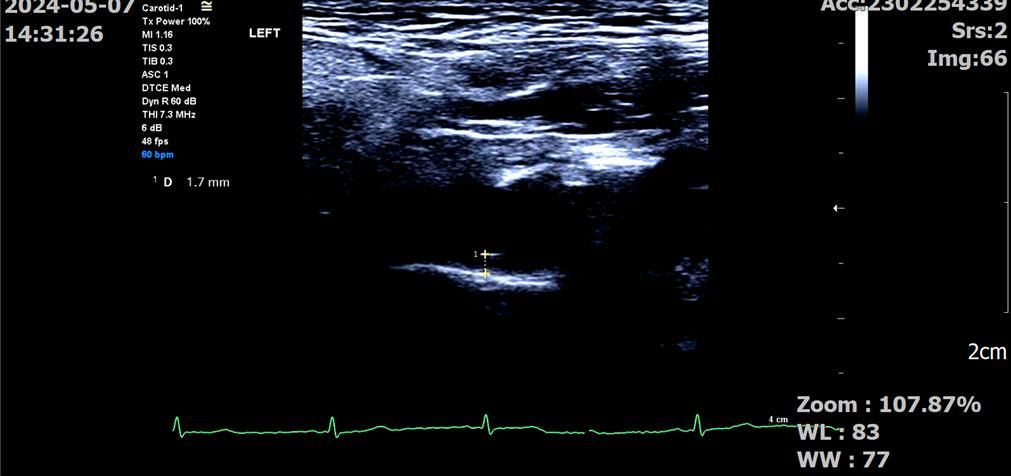

좌측 ICA

병원에서 재 주신 플라크 사이즈는

ICA: 2.0mm, 1.7mm입니다.

정상경동맥 내경을 어떻게 재는지 몰라서 되는 대로 재봤습니다.